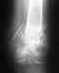

После ДТП перелом обеих лонных и седалищных костей,перелом левой боковой массы кркстца со смещением.Когда наступает полное выздоровление,какие последствия?

Для сколько-нибудь конкретного ответа нужна информация о том, какие именно это переломы, как располагаются фрагменты, как выполнена их фиксация.